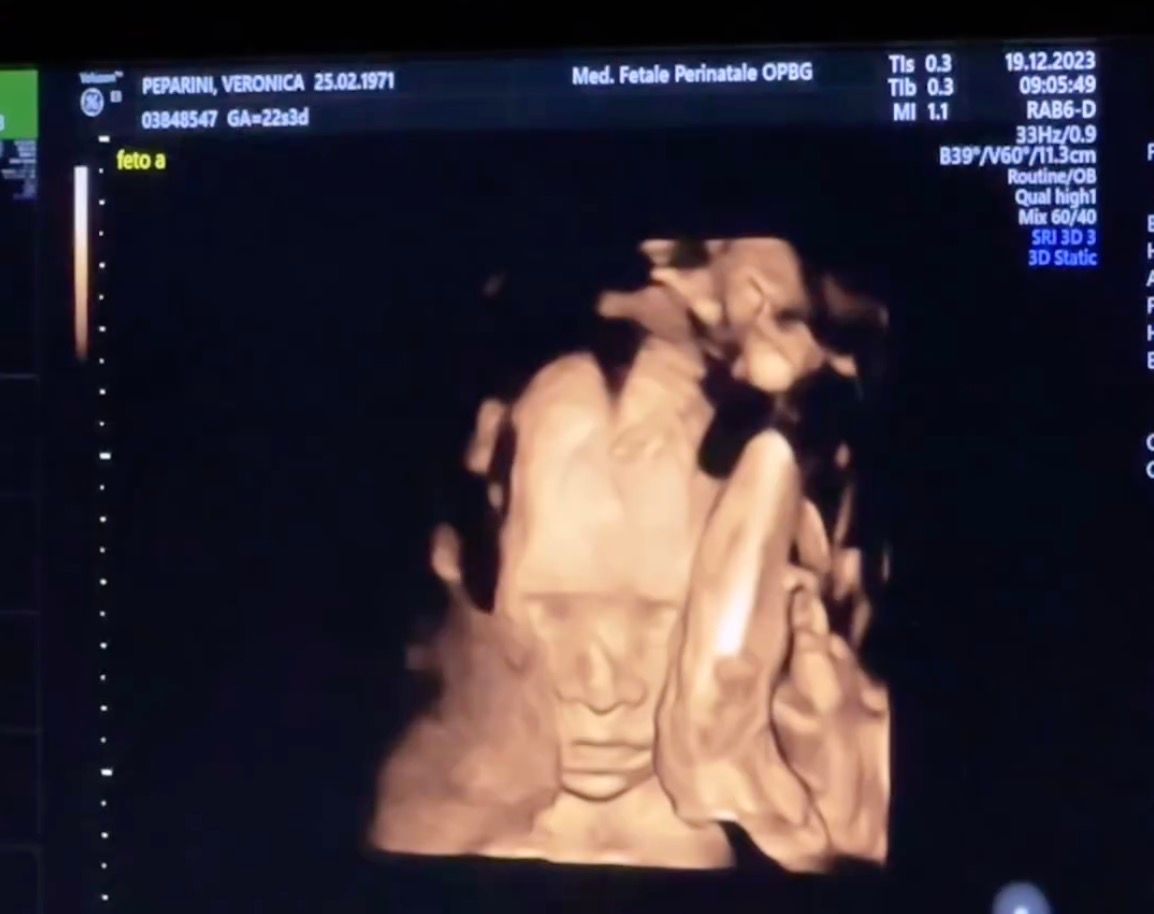

Andreas Muller mostra l’ecografia delle gemelline: “Il nostro regalo di Natale”

Il ballerino pubblica sui social l'ecografia delle bambine che aspetta con Veronica Peparini: “Il nostro regalo di Natale”

Andreas Muller e Veronica Peparini, l'ecografia delle gemelle

Andreas Muller mostra sui social l’ecografia delle gemelline che aspetta con Veronica Peparini.

“Il nostro regalo di Natale”, scrive il ballerino nelle storie su Instagram.